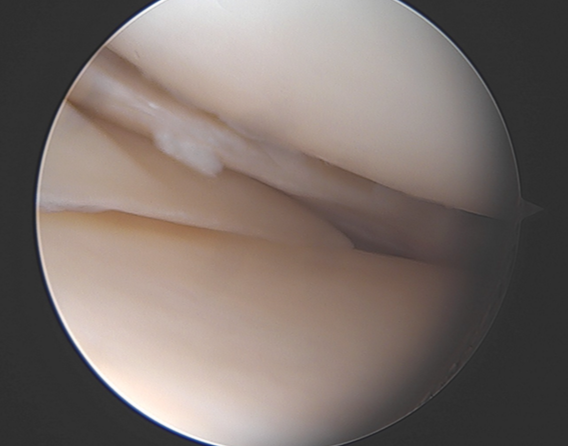

lésion d'un ménisque

On distingue plusieurs lésions des ménisques.

cela consiste à retirer la partie abîmée du ménisque. Cette intervention a lieu en ambulatoire, sous anesthésie générale ou de la jambe. 2 petits orifices en avant du genou permettent d’introduire une caméra et les instruments nécessaires pour retirer les fragments instables.

Cette intervention a lieu en ambulatoire, sous anesthésie générale ou de la jambe. 2 petits orifices en avant du genou permettent d’introduire une caméra et les instruments nécessaires pour réaliser ce geste. Parfois d’autres points d’entrée sont nécessaires.